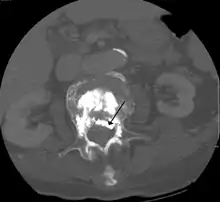

During the procedure, bone cement is injected with a biopsy needle into the collapsed or fractured vertebra. The needle is placed with fluoroscopic x-ray guidance. The cement (most commonly poly methyl methacrylate (PMMA), although more modern cements are used as well) quickly hardens and forms a support structure within the vertebra that provide stabilization and strength. The needle makes a small puncture in the patient's skin that is easily covered with a small bandage after the procedure.[20]